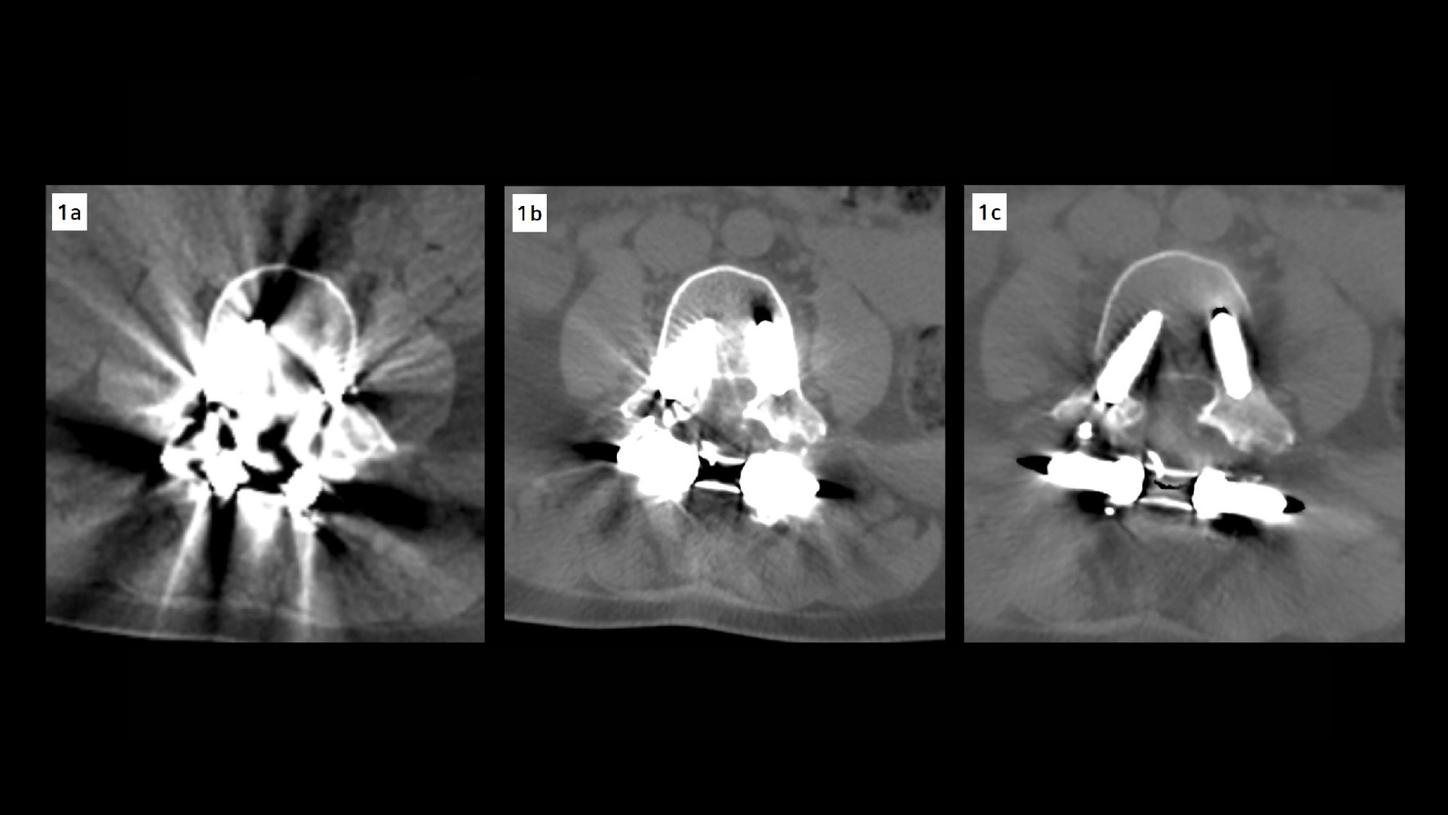

Dual energy CT images with iMAR revealed a fracture of the L4 transpedicular screws and posterior pseudoarthrosis at the L3–L4 level, which were not clearly visible in the previous multislice CT due to extensive metallic artifacts (Fig. 1). Additional findings included diffuse bulging of the L3–L4 intervertebral disc, facet joint nonunion, and posterior fixation hardware contributing to moderate spinal canal stenosis (type C according to Schizas [1] – L3–L4 canal compromise) (Fig. 3). A subarticular and left foraminal protrusion of the L5–S1 disc was also observed, partially occupying the left lateral recess and compressing the exiting nerve root (type D – L5–S1 foraminal impingement) (Fig. 2). The patient is currently being prepared for surgery to address screw failure and pseudoarthrosis. Surgical planning also includes decompression of the L5–S1 nerve root.

Fig. 1: Axial CT images of the lumbar spine at the L3–L4 discal space. (A) Image acquired on a previous standard multislice CT scanner, shows prominent metal artifacts that obscure the vertebral anatomy and prosthetic components. (B) Image reconstructed using iterative metal artifact reduction (iMAR) at 120 kV, demonstrates improved delineation of bone structures and reduction of streak artifacts. (C) Image reconstructed with iMAR combined with high-energy monoenergetic imaging (140 keV), provides superior image quality with markedly reduced metal artifacts and enhanced visualization of the prosthesis and surrounding anatomy.